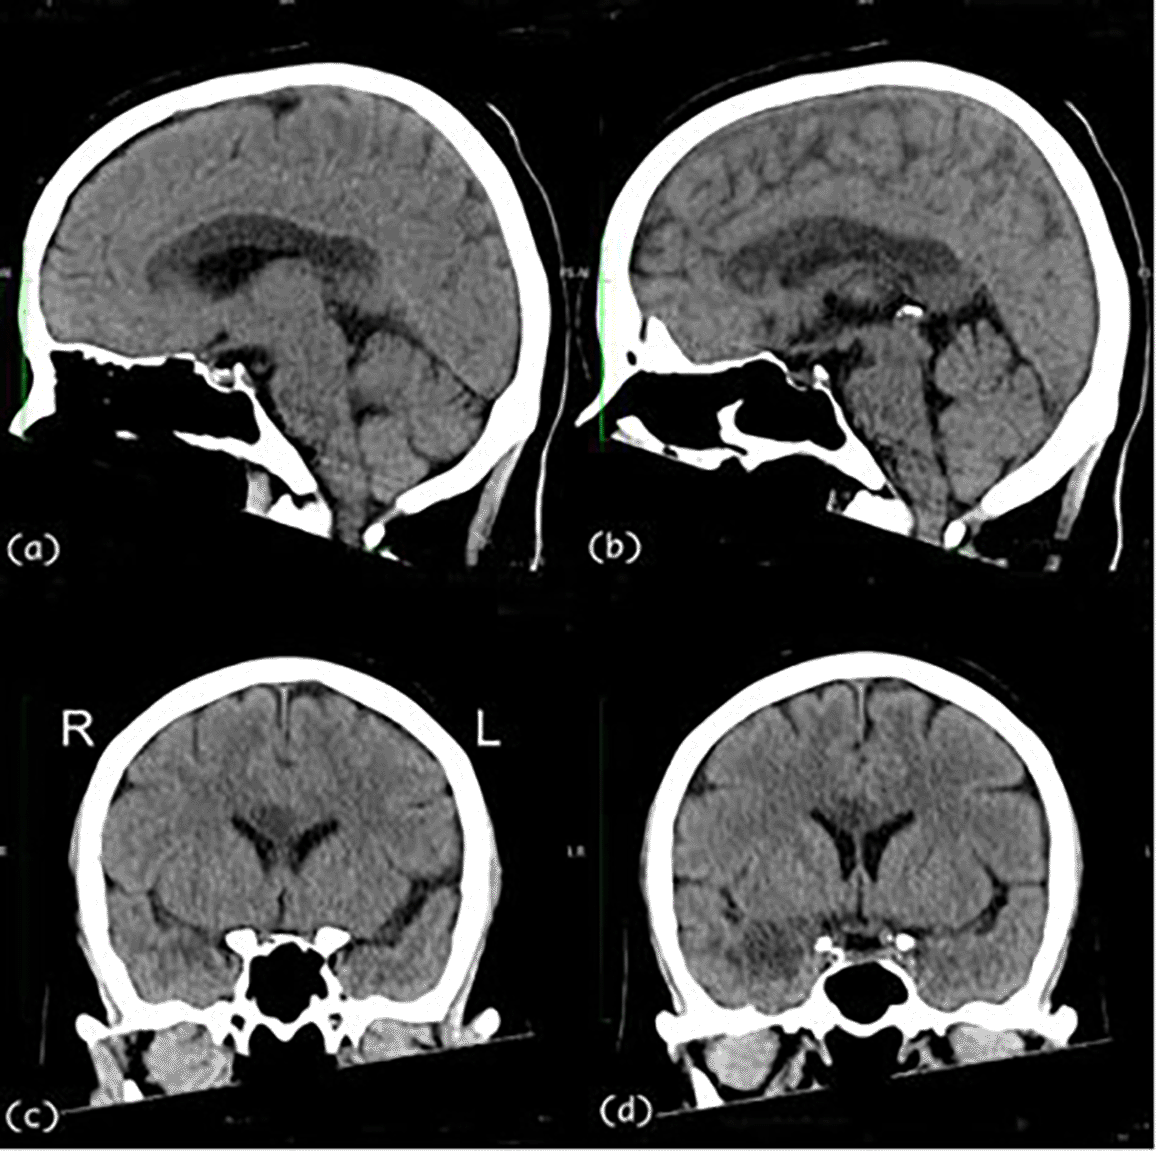

A 57-year-old, right-handed female with risk factors of type II diabetes mellitus and hypertension presented with a sudden onset of left-sided body weakness and slurred speech. The Glasgow Coma Scale (GCS) was 15/15, and her blood pressures were normal. The medical research council (MRC) motor power scale indicated a 4/5 strength in her left upper and lower extremities. Computed tomography (CT) scan of the brain revealed an acute right temporal infarct. The following day, her GCS dropped to 10/15, accompanied by elevated blood pressure. A repeat CT scan displayed an evolution of the right temporal infarct and a new acute corpus callosum infarct extending from the right genu to the left side of the splenium (Figure 1 and Figure 2). Subsequent CT angiography (CTA) revealed short segment stenosis of the proximal M1 segment of the right middle cerebral artery (MCA), left fetal PCA, and hypoplastic right posterior communicating (PCOM) artery. Three weeks post-stroke, she was transferred to the rehabilitation unit.

The CT images demonstrate an extensive hypodensity from genu to the splenium of the corpus callosum and the right temporal lobe. CT, computed tomography.